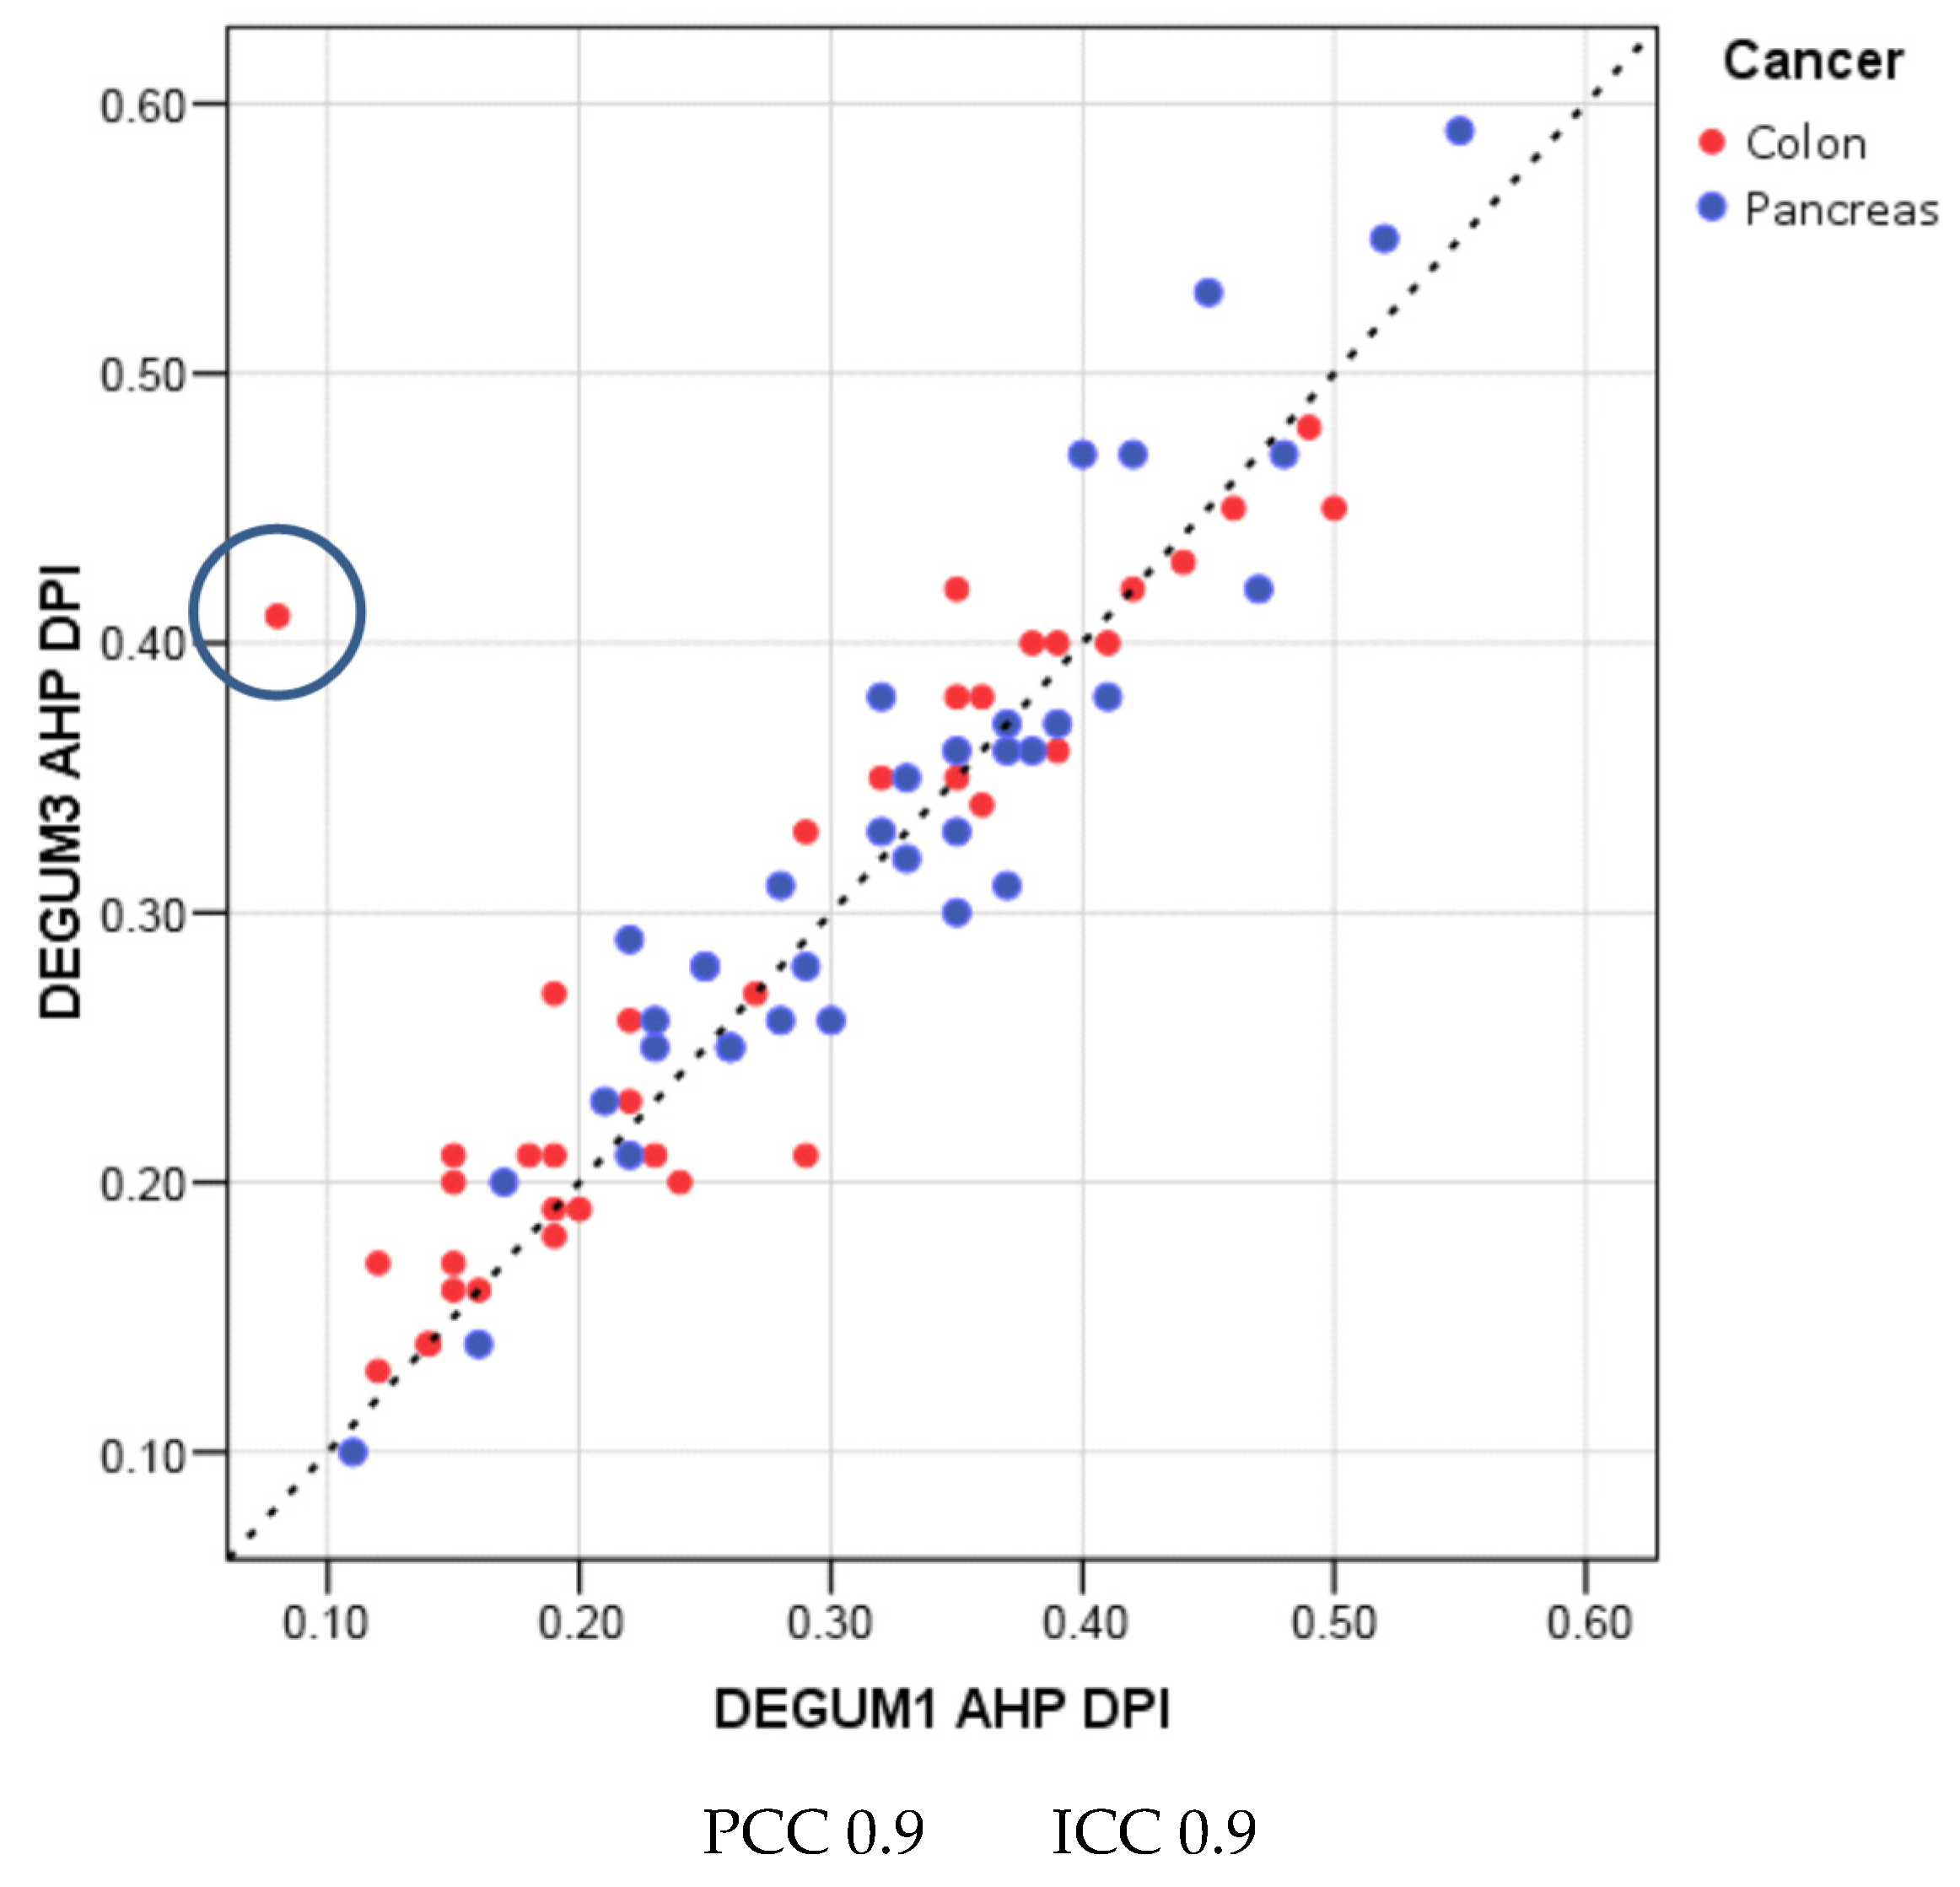

| Parameter | Diameter [mm] | Insonation Angle | Doppler Shift [cm/s] | Flow [mL/min] | AHP-DPI |

|---|---|---|---|---|---|

| N | 79 | 76 | 76 | 76 | 76 |

| Mean D1 (SD) | 4.4 (0.7) | 35.8 (16.9) | 24.6 (11.3) | 308 (165) | 0.3 (0.1) |

| Mean D3 (SD) | 4.5 (0.7) | 36.6 (17.3) | 25 (9.4) | 332 (166) | 0.3 (0.1) |

| Mean tot (SD) | 4.5 (0.7) | 36.2 (17) | 24.8 (10.3) | 320 (165) | 0.3 (0.1) |

| Mean Diff (SD) | 0.1 (0.4) | 0.8 (14.9) | 0.5 (8.5) | 24 (86) | 0.01 (0.05) |

| p(Bias) | 0.10 | 0.98 | 0.14 | 0.05 | 0.06 |

| p(Var) | 0.38 | 0.33 | 0.25 | 0.94 | 0.66 |

| PCC | 0.81 | 0.62 | 0.68 | 0.87 | 0.90 |

| ICC (95% CI) | 0.81 (0.71; 0.87) | 0.62 (0.46; 0.74) | 0.67 (0.52; 0.78) | 0.86 (0.78; 0.91) | 0.90 (0.84; 0.93) |

| MVC | 0.05 | 0.27 | 0.15 | 0.13 | 0.08 |

| B/A Limits | (−0.79; 0.94) | (−28.5; 30.1) | (−16.1; 17.0) | (−145; 192) | (−0.09; 0.11) |